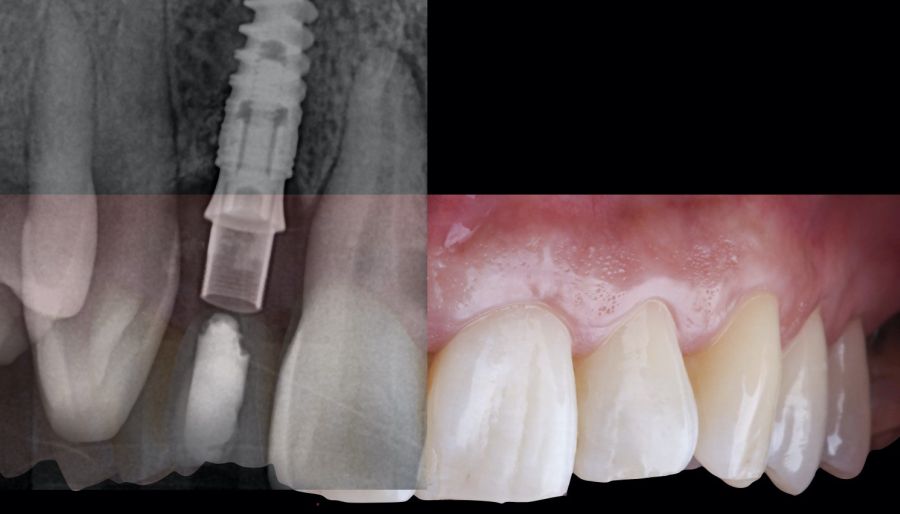

* Phase II: healing proceeded without complications. After 5 months from the alveolar preservation surgery, guided implant surgery was planned at position 1.2 (Figure 2). For this purpose, a DICOM file from cone beam computed tomography (CBCT) and an STL file obtained from scanning with an intraoral optical scanner were used. Using this information, a dental support surgical guide was fabricated (Figure 3). The surgical guide was anchored onto the teeth and guided the preparation of the implant bed and the placement of the implant. The guided surgery technique consisted of flap surgery, preparing and inserting the implant (3.5 x 11.5 mm) according to the standardised Nobel Active® guided surgery protocol (Nobel Biocare AB, Gothenburg, Sweden). Once implant 1.2 was placed,a gingival graft composed of epithelium and connective tissue from the palatal masticatory mucosa was obtained. Subsequently, the superficial epithelial layer of this graft was deepithelialised extraorally using a 15C scalpel blade in order to obtain a connective tissue graft from the underlying layer18.

* Phase III: three months after implant placement, the soft tissue condition was favourable (Figures 5 and 6). A digital impression was obtained using an intraoral scanner for the fabrication of a screwretained

polymethyl methacrylate (PMMA) provisional restoration. Regarding the definitive

implant crown, a cement-screw-retained

restoration was fabricated with a titanium nitride interface, adapting the design to the emergence profile already consolidated with the provisional prosthesis. The crown was produced by CAD-CAM in zirconia with full reduction and feldspathic ceramic veneering for zirconia (Figure 7).